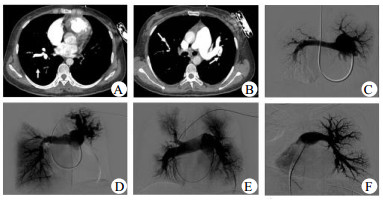

2.2 影像学和动脉受累情况CTPA和动脉造影示所有患者均肺动脉受累,且均累及双侧肺动脉。8例主肺动脉扩张,其中2例呈瘤样扩张。双侧肺动脉主干可同时受累,也可单个受累。受累血管多表现为狭窄或扩张。2例右肺动脉主干完全闭塞。每个患者均多个叶、段以及亚段肺动脉受累,表现为不同程度血管狭窄、血管壁增厚,管腔纤细、扩张、粗细不等,或动脉瘤,且DSA肺动脉造影见血管走形扭曲、僵硬,远端灌注稀疏或消失(图 1)。

| A:右中下叶肺动脉扩张,部分分支局限性狭窄,左下肺动脉未显影,提示血管完全闭塞;B:主肺动脉增宽,左侧肺动脉近段扩张、扭曲,右上肺动脉纤细,血管影稀疏;C:主肺动脉增宽,左肺动脉及分支纤细,远端灌注稀疏甚至缺失,右肺动脉远端动脉瘤,右上、中叶肺动脉僵硬,远端灌注稀疏,右下肺动脉缺如;D:肺动脉主干明显增粗,右上叶及左下叶肺动脉缺如,左上肺动脉瘤样扩张、扭曲,灌注略稀疏,右中下肺动脉近端多处狭窄,未见明显充盈缺损,远端灌注良好;E:主肺动脉和左右肺动脉增粗,右上叶前段肺动脉狭窄后闭塞,尖后段血管僵硬,远端灌注稀疏,右下叶肺动脉扩张,段肺动脉远端纤细、闭塞,灌注稀疏;左侧叶段肺动脉管腔通畅,远端灌注稍稀疏;F:左肺动脉及左侧各叶段肺动脉连续性扩张-狭窄-扩张样表现,即串珠样表现,血管僵硬,远端灌注稀疏 图 1 大动脉炎肺部累及的影像学表现 Figure 1 Images of pulmonary artery involvement in TA |